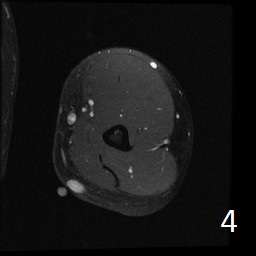

Angiolipoma is a subcutaneous benign tumor, made up of mature fat and blood vessels that often presents as multiple lesions. It sometimes arises intramuscularly. The incidence may be associated with familial heritage, close to 5% of the cases. Angiolipomas often arise in young patients, shortly before puberty, and are rarely seen in younger children or older adults. Angiolipomas often present as single or multiple subcutaneous tender to painful nodules (especially multiple ones). The pain may decrease as the lesion ages. No preference for ages or gender. Sites more commonly affected are the upper extremity and trunk, but rarely can affect head and neck region. MRI shows homogeneous and well circumscribed lesion, with intermediated signal on T1w (Fig. 1) and increased signal on T2W (Fig. 2). On fat suppress sequences the tumor may not suppress completely necause of its vascularity (Fig. 3). There is significant enhancement post contrast images (Fig. 4). On gross pathology the mass is a circumscribed, yellow-red nodular mass due high fat content and blood vessel proliferation. Microscopically, shows mature fat cells separated by branching network of small blood vessels, more prominent in subcapsular areas; there are usually associated fibrin thrombi (important sign). Adipocytes and interspersed vascular structures are seen, lined by elongated endothelial cells. These cells are irregular, and fingerlike extensions surrounded by periytes. Angiolipoma is a benign mass. It does not exhibit aggressive behavior. It rarely shows recurrence after resection. The treatment is complete surgical excision.

Fig. 1-4: Axial MRI of the arm shows a well circumscribed mass with intermediate signal on T1W (Fig. 1), and increased in T2W (Fig. 2). Fig. 3 Axial T1W FS shows a lesion and moderate intense on T1WFS post contrast (Fig. 4).